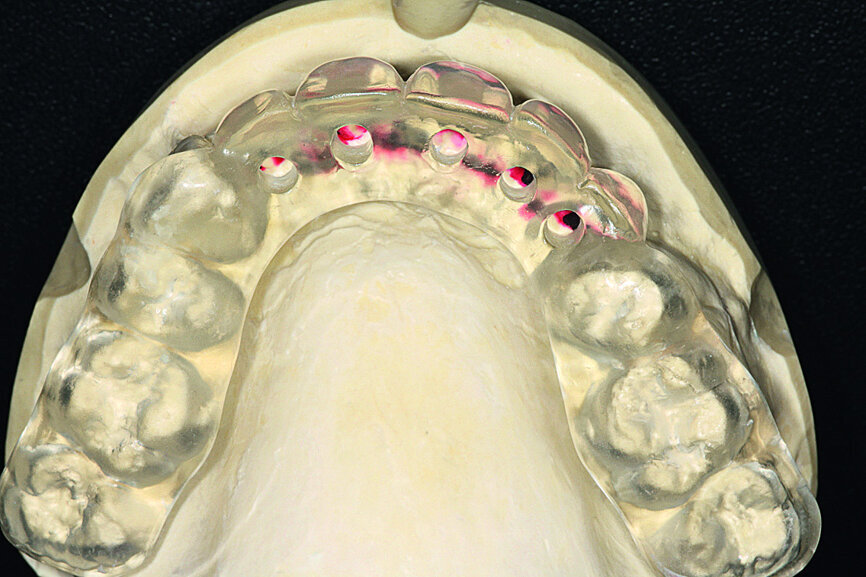

Fig. 12: A key of the added wax was taken and fabricated in clear casting resin.

Pre-implant prosthetic study

After four months, according to radiographic examination, the tissue had healed and the bone mass appeared stable (Fig. 10). New impressions were taken to prepare for the next step in treatment: the implant drilling guide. After four months of healing, the increased vestibular bone volume allowed positioning the teeth at the crestal bone and reduction of the false gingiva using additional wax (Fig. 11). A key of the added wax was taken and fabricated in clear casting resin. The implant positions were decided on and finalised by drilling placement holes, determining the exact position of the implants (Fig. 12). The correct positioning of implants in relation to the future prothesis is an important prerequisite for aesthetic and functional success.